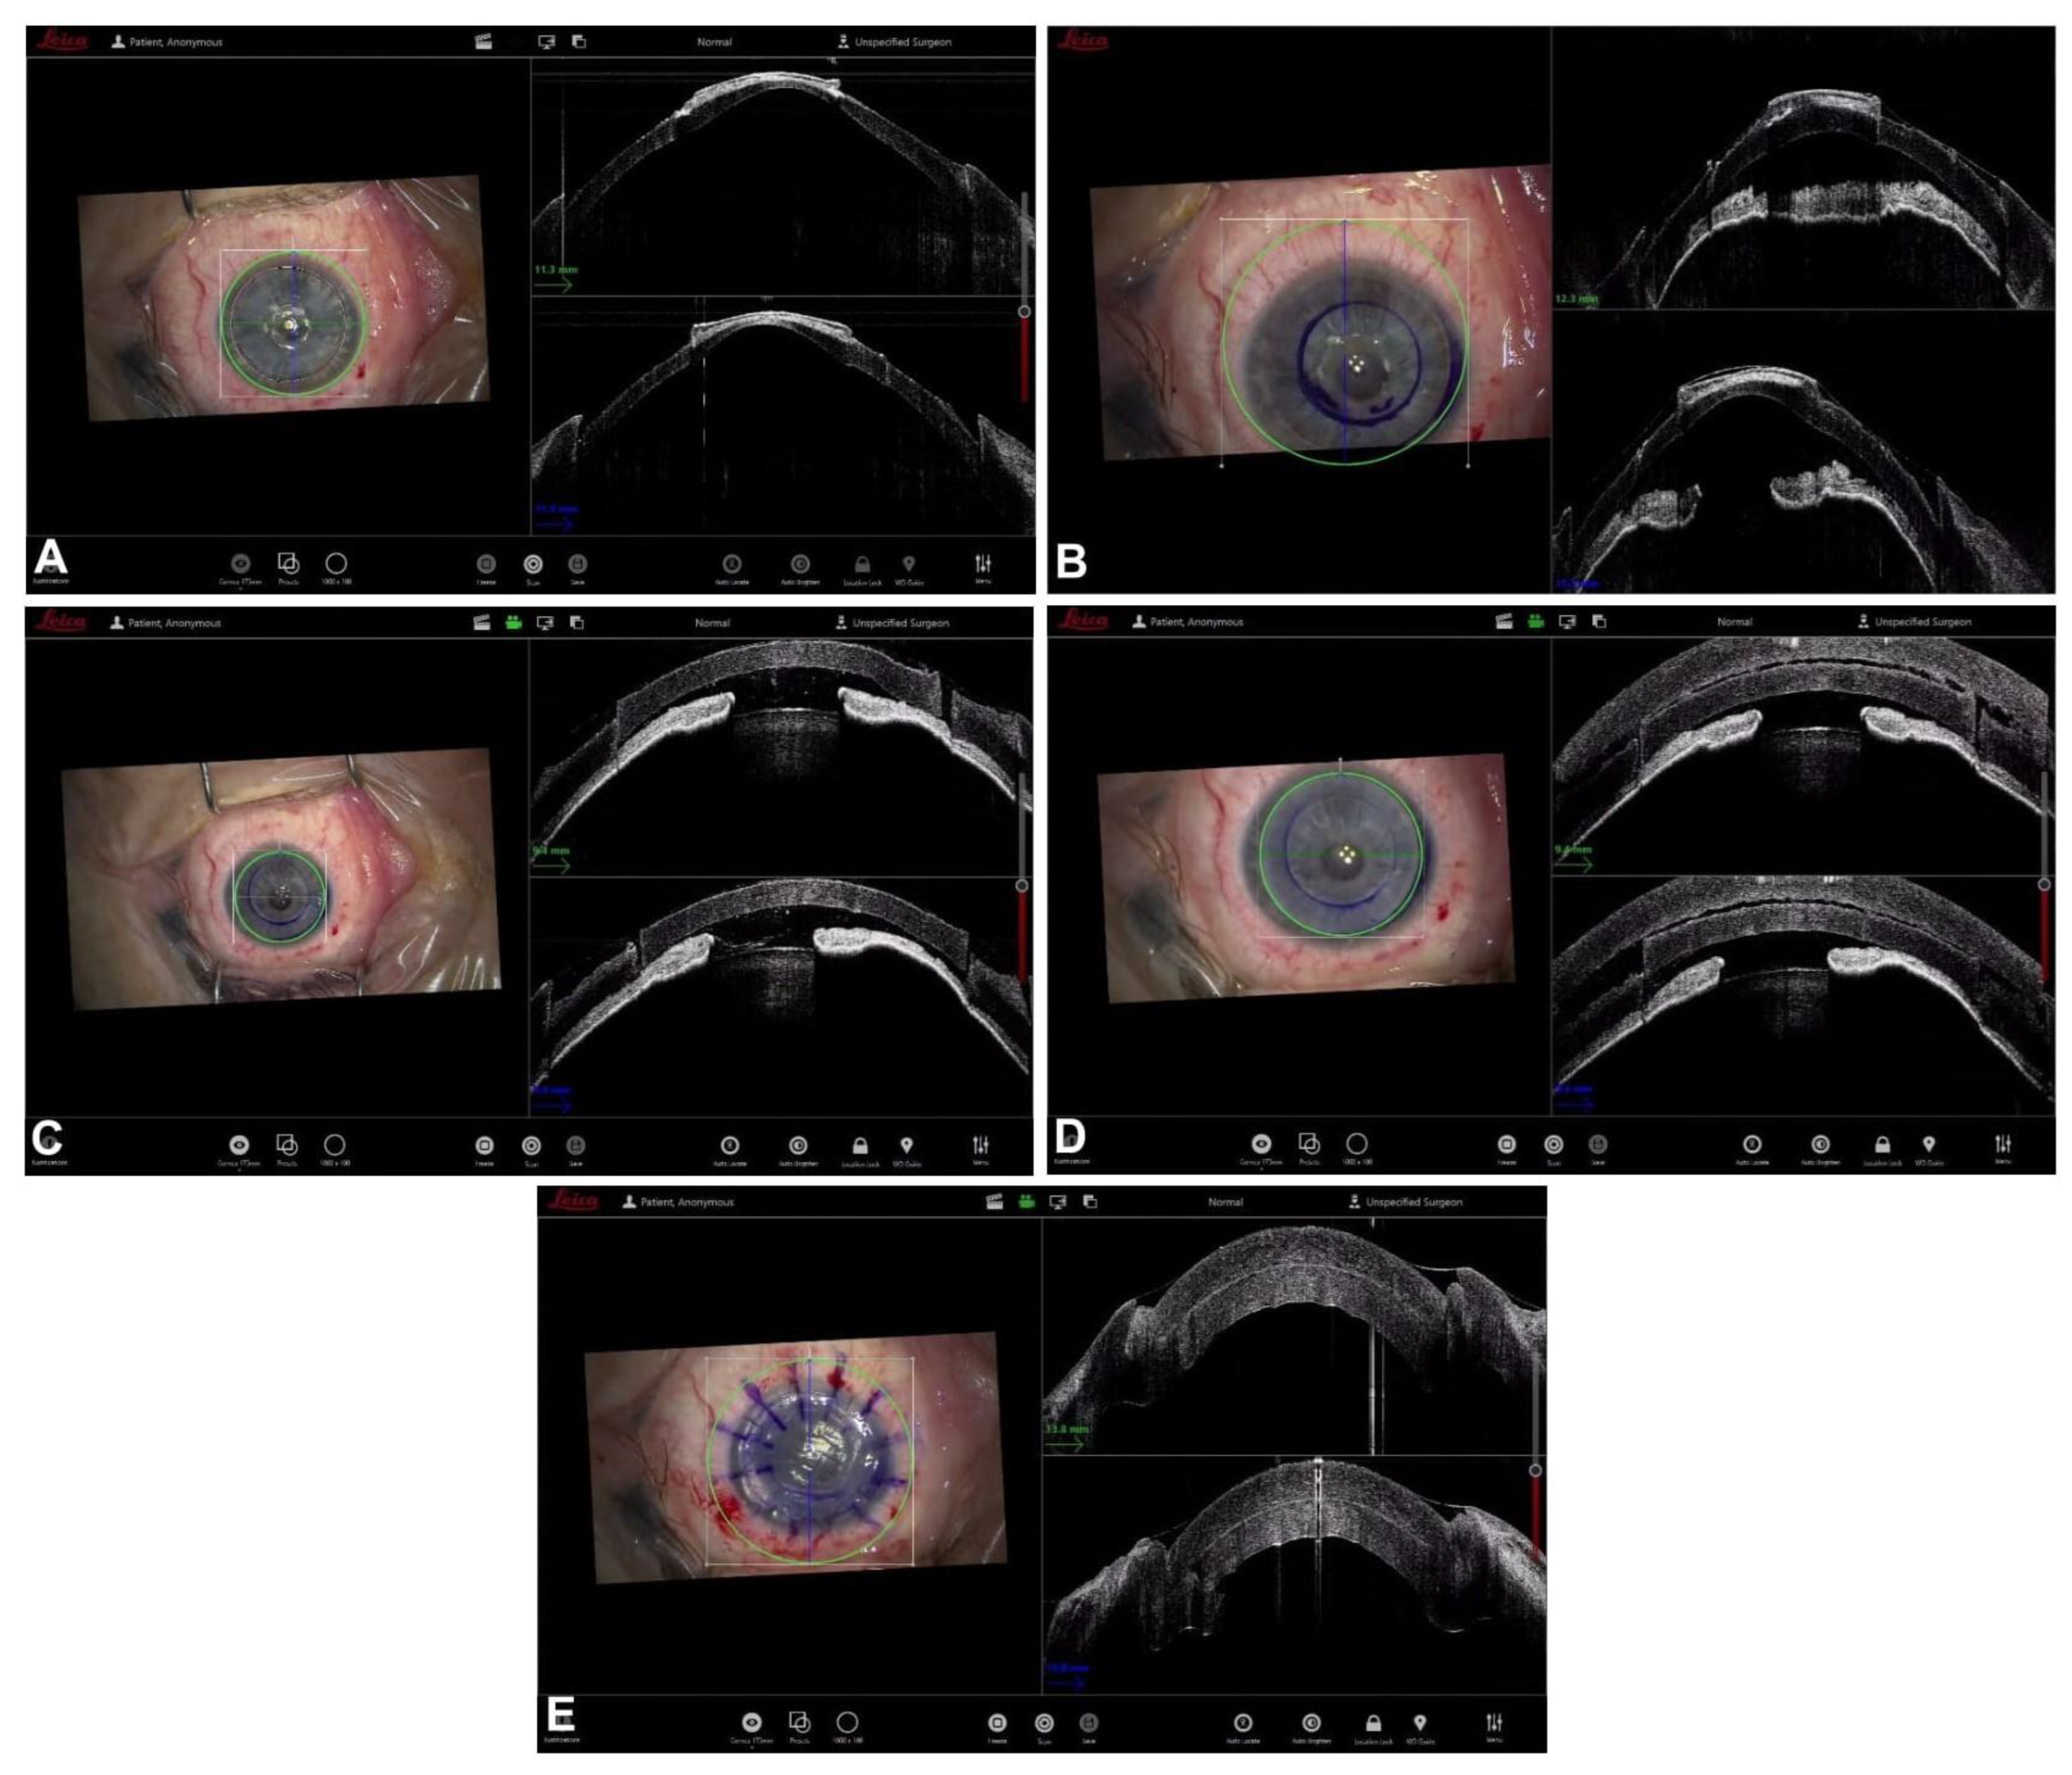

5. Guiding Descemet Membrane Endothelial Keratoplasty

- Steven, P.; Le Blanc, C.; Velten, K.; Lankenau, E.; Krug, M.; Oelckers, S.; Heindl, L.M.; Gehlsen, U.; Hüttmann, G.; Cursiefen, C. Optimizing Descemet Membrane Endothelial Keratoplasty Using Intraoperative Optical Coherence Tomography. JAMA Ophthalmol. 2013, 131, 1135–1142. [Google Scholar] [CrossRef] [PubMed]

- Sharma, N.; Sahay, P.; Maharana, P.K.; Kumar, P.; Ahsan, S.; Titiyal, J.S. Microscope Integrated Intraoperative Optical Coherence Tomography-Guided DMEK in Corneas with Poor Visualization. Clin. Ophthalmol. 2020, 14, 643–651. [Google Scholar] [CrossRef] [PubMed]

- Patel, A.S.; Goshe, J.M.; Srivastava, S.K.; Ehlers, J.P. Intraoperative Optical Coherence Tomography–Assisted Descemet Membrane Endothelial Keratoplasty in the DISCOVER Study: First 100 Cases. Am. J. Ophthalmol. 2019, 210, 167–173. [Google Scholar] [CrossRef]

- Muijzer, M.B.; Soeters, N.; Godefrooij, D.A.; van Luijk, C.M.; Wisse, R.P.L. Intraoperative Optical Coherence Tomography–Assisted Descemet Membrane Endothelial Keratoplasty: Toward More Efficient, Safer Surgery. Cornea 2020, 39, 674–679. [Google Scholar] [CrossRef] [PubMed]

- Cost, B.; Goshe, J.M.; Srivastava, S.; Ehlers, J.P. Intraoperative Optical Coherence Tomography–Assisted Descemet Membrane Endothelial Keratoplasty in the DISCOVER Study. Am. J. Ophthalmol. 2015, 160, 430–437. [Google Scholar] [CrossRef] [PubMed]

- Muijzer, M.B.; Heslinga, F.G.; Couwenberg, F.; Noordmans, H.-J.; Oahalou, A.; Pluim, J.P.W.; Veta, M.; Wisse, R.P.L. Automatic evaluation of graft orientation during Descemet membrane endothelial keratoplasty using intraoperative OCT. Biomed. Opt. Express 2022, 13, 2683. [Google Scholar] [CrossRef] [PubMed]